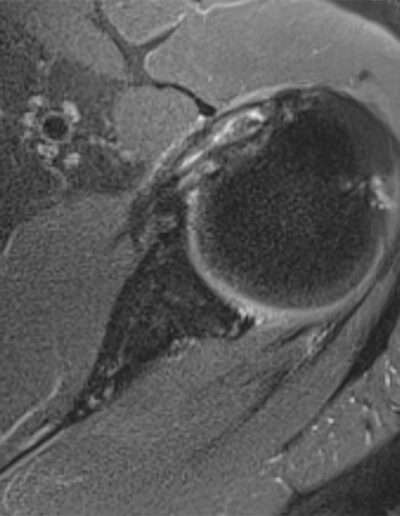

SHOULDER CASE SUMMARY:

Shoulder Left

Patient 55 y/o, Male, left-handed

History Shoulder pain for 3 years